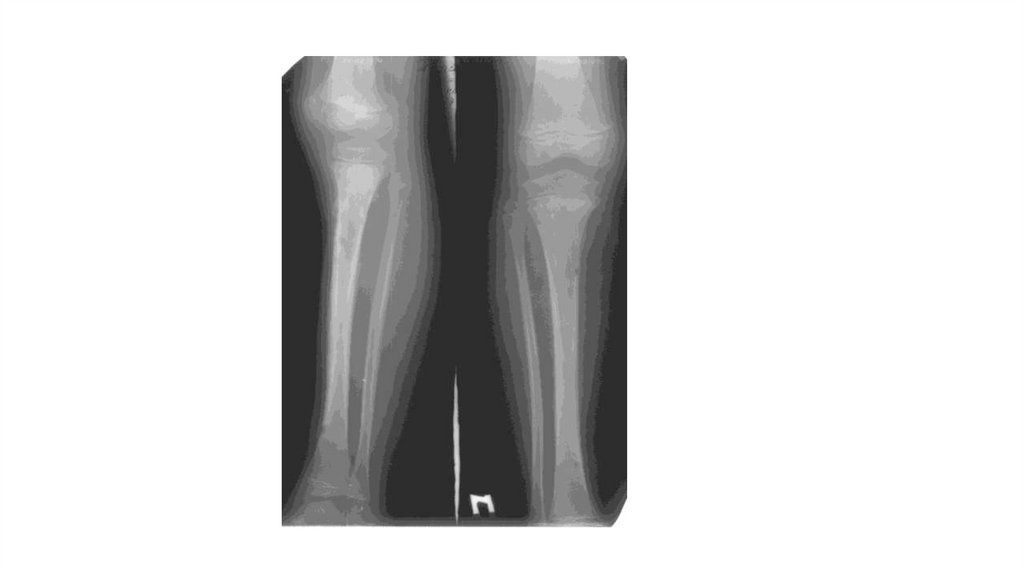

Воспалительные заболевания опорнодвигательного аппарата

«Воспалительные

заболевания опорнодвигательного аппарата»